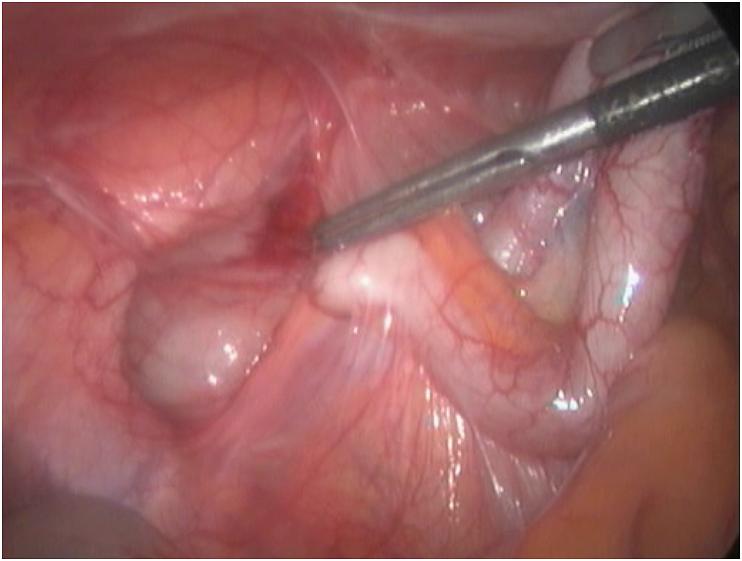

Congenital agenesis of the gall bladder is a very rare ranging from 0.02% to 0.002% in clinical practice. There is complete absence of the gall bladder with normal intra and extra hepatic biliary tree. The exact etiology remains unclear. Low index of suspicion and failure of routine investigations will result in its unexpected discovery during surgery. The condition usually results in diagnostic dilemma both before surgery and intraoperatively. A 25-year-old lady presented with repeated attacks of right side abdominal pain for 1 year. Abdominal examination showed tenderness on palpation in the right hypochonrdium. Abdominal ultrasound showed normal common bile duct with suspicion of small contacted gall bladder. MRCP showed extrahepatic biliary tree and not visualized gall bladder. During diagnostic laparoscopy exploration of the whole peritoneal cavity was performed. The gall bladder was not visualized after complete visualization of biliary anatomy. The appendix was inflamed with multiple adhesions with the bowel. The cecum was high placed in the sub-hepatic region. Laparoscopic appendicectomy was performed. Patients with gall bladder agenesis surprisingly have symptoms similar to cholecystitis, the pain may be attributed to cholangitis, biliary stones, or sphincter of Oddi dysfunction. When the condition diagnosed at operation extensive dissection to identify the gall bladder must be avoided because it may result in biliary injury.

先天性胆囊缺如是一种非常罕见的疾病,在临床实践中的发生率为0.02%至0.002%。胆囊完全缺失,肝内和肝外胆管树正常。确切病因尚不清楚。怀疑指数低和常规检查失败会导致在手术期间意外发现该病。这种情况通常会在手术前和手术中导致诊断困境。一名25岁女性因右侧腹痛反复发作1年前来就诊。腹部检查显示右季肋部触诊有压痛。腹部超声显示胆总管正常,怀疑有小的收缩胆囊。磁共振胰胆管造影(MRCP)显示肝外胆管树,未显示胆囊。在诊断性腹腔镜检查中,对整个腹腔进行了探查。在完全观察到胆管解剖结构后,未发现胆囊。阑尾发炎,与肠管有多处粘连。盲肠高位位于肝下区域。进行了腹腔镜阑尾切除术。胆囊缺如的患者令人惊讶地出现与胆囊炎相似的症状,疼痛可能归因于胆管炎、胆结石或Oddi括约肌功能障碍。当在手术中诊断出这种情况时,必须避免进行广泛的解剖以寻找胆囊,因为这可能导致胆管损伤。